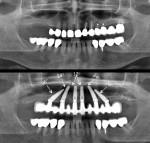

Without exception, all cases should be screw-retained and not cemented. This is made possible through the use of external hexed Co-Axis® implants (Southern Implants, southernimplants.com) with 12°, 24°, and 36° subcrestal angle correction (Figure 1). Screw retention enables retrievability for prosthetic maintenance. Additionally, there is no cement to deal with in the immediate loading environment, and there is no chance for cement-induced peri-implantitis.

Placement of multi-unit abutments at the time of surgery (one abutment/one-time concept)3 is preferable in most multiple-implant cases unless inadequate prosthetic space dictates that the prosthesis connects directly at implant level. Furthermore, with subcrestal angle correction using 12°, 24°, and 36° Co-Axis implants, straight/0° multi-unit abutments can be used in place of cumbersome, prosthetic space-consuming 17° and 30° angled abutments (Figure 2). Multi-unit abutments result in less bone loss and increased comfort for the patient during connection/disconnection of the prosthesis.4